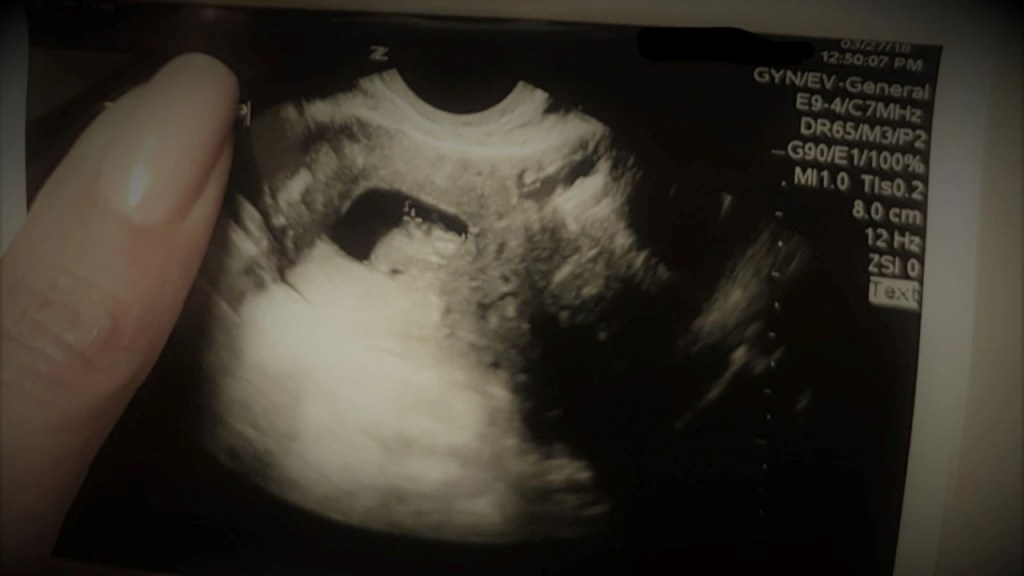

In my research, I argue endometriosis is an invisible illness, one that tends to be unseen by medical experts—sometimes literally, as diagnosis is made by cutting into the abdomen and extracting tissue to send to the pathologist, who then confirms the presence of endometrial cells. For decades it was also a disease invisible in our society, in that most people experiencing the agony of the disease were dismissed, their pain deemed irrelevant, and their suffering chalked up to simply “being a woman.”